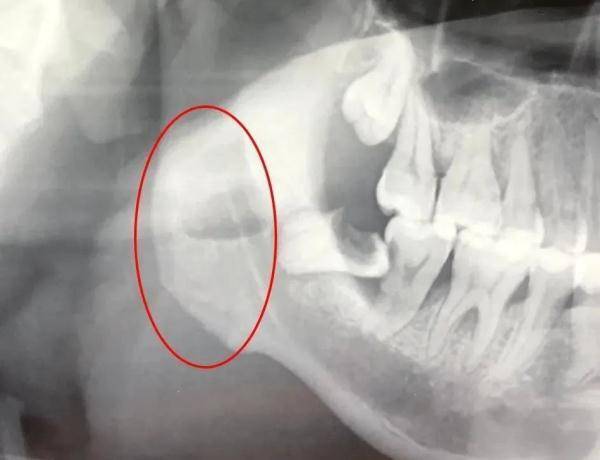

一颗烂掉的智齿发炎十多天,引发颌面部多间隙感染,炎症向下扩散至颈部及前胸,余先生在(湖北)武汉大学口腔医院接受切排引流手术并拔除智齿后,被送入ICU重症监护室24小时监护。

急诊科副主任医师赵丹、创伤外科副主任医师吕坤接诊后,通过口腔检查和CT辅助检查,诊断他为颌面部间隙感染,建议他立即住院手术治疗,可余先生放不下工期,只请医生做了简单处理,便回家了。

“患者血检报告单中,白细胞数值远超过正常值,感染正在向颈、胸部扩散,引起了胸部疼痛表现,而他空腹血糖指标高达14.25mmol/L、尿糖3+,之前可能存在未察觉的糖尿病。”

吕坤指出,患糖尿病的病人抵抗力较差,身体组织和血液里糖分较高,比普通人更容易引发炎症的感染和扩散,再不手术排脓,恐怕颈部肿胀加重压迫呼吸,向下引发纵膈脓肿、败血症等危及生命。

7月1日,余先生接受手术。术前,麻醉医生先给他注射胰岛素,将血糖尽量控制在全麻要求范围内;随后,吕坤为余先生拔掉发炎的智齿,将颌面颈部多个间隙里的脓肿切开引流。